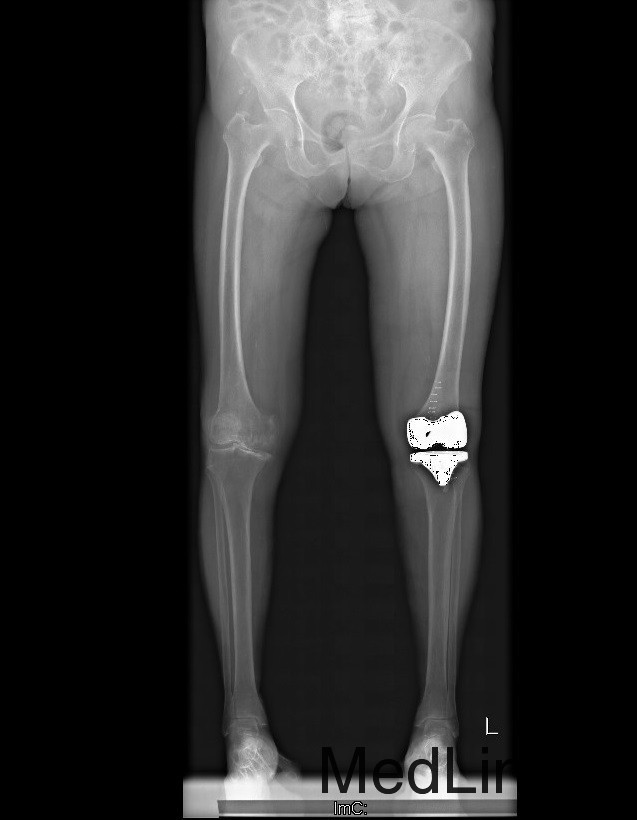

主诉:双膝疼痛20年,加重伴行走困难8年 现病史:20年前患者开始出现双膝关节疼痛,负重行走、下楼时疼痛加重,休息后可缓解,尚可下蹲。,自行购买口服止痛药,关节腔内注射玻璃酸钠、理疗等处理,疼痛时有缓解。但症状反复发作。8年前疼痛加重且行走困难,扶拐行走仅能坚持约10余米,上下楼梯艰难,下蹲不能,以左侧为重。现患者为行进一步治疗入院。

查体:查体:跛行步态,双膝关节屈曲内翻畸形,双膝内侧间隙压痛,双膝髌股关节间隙压痛,左膝伸-20°,屈110°内翻10°。右膝伸-20°,屈110°内翻10°,双膝屈伸活动时髌骨下摩擦感(+)。 辅助检查:双侧髌股关节内侧间室变窄,关节边缘骨赘增生,软骨下骨硬化。

诊断:1、双膝骨关节炎伴屈曲内翻畸形 左侧重2、高血压病(2级高危、) 治疗:在全麻下行左侧全膝关节置换术+软组织松解术,术后予以抗炎+抗凝+镇痛+补液+护胃治疗,并指导其功能锻炼。

1、患者术后屈曲110°,伸0°,下地行走正常。 讨论 1、患者髌骨位置如何,术中有哪些方法避免术后低位髌骨 2、股骨曲度较大的患者,股骨截骨有何注意点